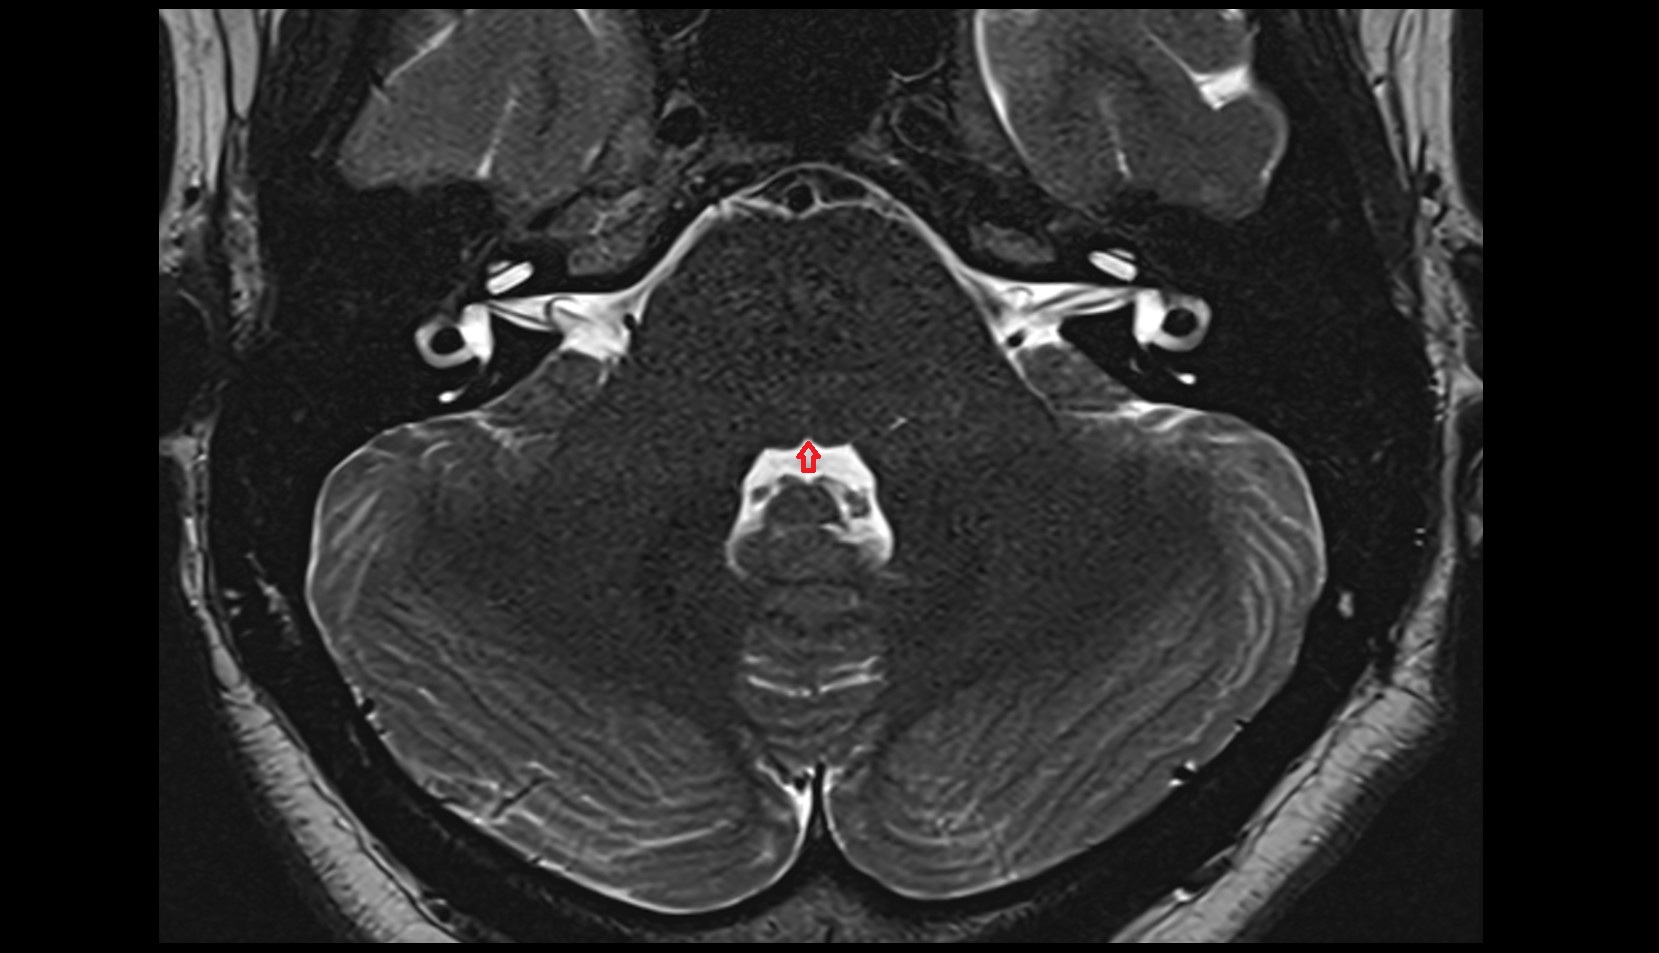

- Median aperture of fourth ventricle (foramen of Magendie)

- Lateral aperture of fourth ventricle (foramen of Luschka)